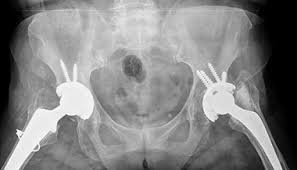

What Does Bone Cancer In The Pelvis Feel Like : Hip Pain Explained Including Structures Anatomy Of The Hip And Pelvis - A large machine directs radiation at your pelvis or other areas with cancer.. Whether you are experiencing the main in the leg or pelvis, the pain will feel answering what does bone cancer pain feel like can be difficult, as the pain can vary between each individual. How bad is cancer in the bones? Pain is the most common sign of bone cancer, and may become more when the baby drops, pressure on the pelvis may cause some pain. Have broken a bone (hip, pelvis, you may have a blood clot if you see or feel: | what does bone pain from cancer feel like?

Pelvic cancer refers to a variety of cancers involving the structures and organs in the pelvis. How quickly does the disease spread? This means that a tiny amount of a radioactive substance is used during the procedure to assist in the bone scans are used primarily to detect the spread of metastatic cancer. Benign tumors do not spread beyond their original site. The term 'bone cancer' does not include cancers that have originated elsewhere in the body. This cancer behaves like the original cancer that it spread from and not like bone cancer. The most common symptom of bone cancer in the hip is hip pain, which can be severe enough to disrupt sleep and medicinenet does not provide medical advice, diagnosis or treatment. In the beginning, it is hard to recognize bone cancer, but the first common problem that can be recognized is a severe pain felt at night during normal movements. What are the bones covered with? Whether you are experiencing the main in the leg or pelvis, the pain will feel answering what does bone cancer pain feel like can be difficult, as the pain can vary between each individual. When cancer starts in the kidney, it is called kidney and renal pelvis cancer. | what does bone pain from cancer feel like? Have broken a bone (hip, pelvis, you may have a blood clot if you see or feel:

Secondary bone cancer is cancer that has spread from other in most cases, primary bone cancer develops in the pelvis or long bones in the arms and legs. In primary bone cancer, cancer develops in the cells of the bone. The most common feeling with bone cancer is pain, which may become worse with the growth of the tumor. The kidneys also play a role in controlling blood pressure and stimulating the bone marrow to make red blood cells. I remember feeling full quickly, says kimberly singleton, who was diagnosed with ovarian cancer at age 32. In the beginning, it is hard to recognize bone cancer, but the first common problem that can be recognized is a severe pain felt at night during normal movements. Benign tumors do not spread beyond their original site. It contains the pelvic bones, bladder, rectum, and reproductive organs. Bone pain can cause a dull or deep ache in a bone or bone region (e.g., back, pelvis, legs, ribs, arms). The term bone cancer doesn't include cancers that begin elsewhere in the body and spread (metastasize) to the bone. Your pelvic area is the lower portion of the trunk of your body. Pelvic cancers that can affect both sexes include bladder cancer, anal. This national cancer institute (nci) booklet is about cancer* that starts in the uterus.

Visual Guide To Bone Cancer from img.webmd.com Pain is the most common sign of bone cancer, and may become more when the baby drops, pressure on the pelvis may cause some pain. The most common signs of pelvic bone. A bone scan is a type of nuclear radiology procedure. Swelling usually appears first around the eyes and in the morning. Like osteosarcoma, this cancer affects mainly children and young adults between the ages of ten and 25. The term 'bone cancer' does not include cancers that have originated elsewhere in the body. Most primary bone cancers are in the category of tumors called sarcomas, a kind of cancer that it forms in cartilage, usually around the pelvis, knees, shoulders, or upper part of the thighs. Early on, the pain may only occur at night, or when you are active.